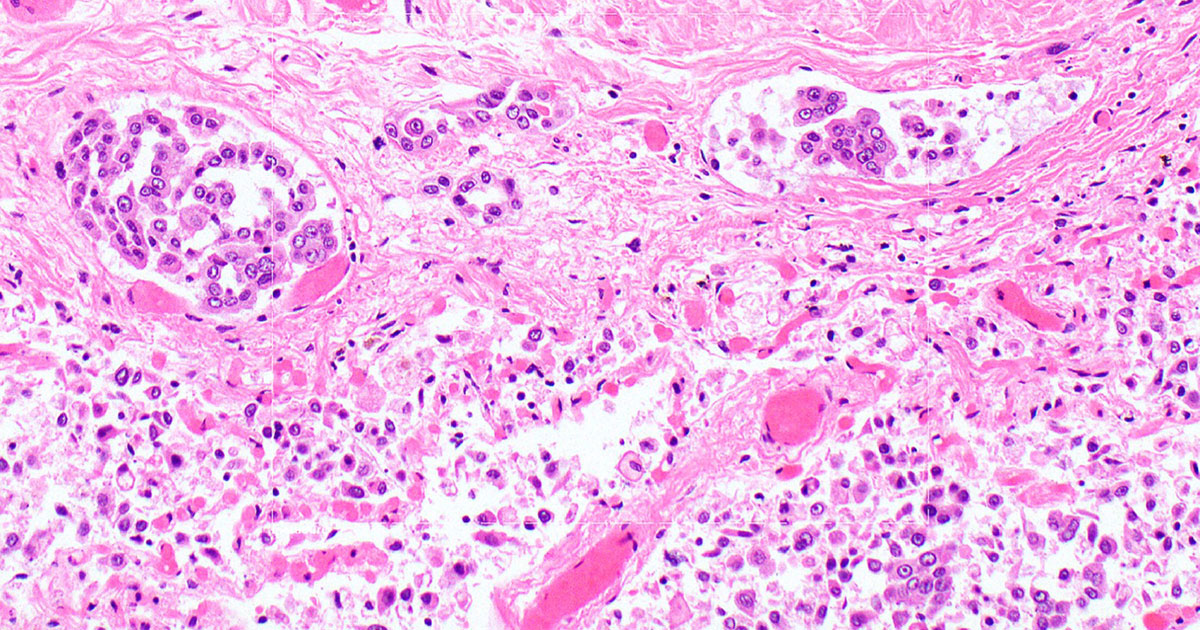

Pathology Report Excerpt Confirming Mesothelioma Diagnosis

This post documents a limited excerpt from a pathology report confirming the diagnosis of malignant mesothelioma in Dorothy Lillian Jay. The image shown below is a partial, redacted excerpt of the original pathology report. The full report is not published in order to protect medical privacy and because only specific diagnostic confirmation is relevant to…